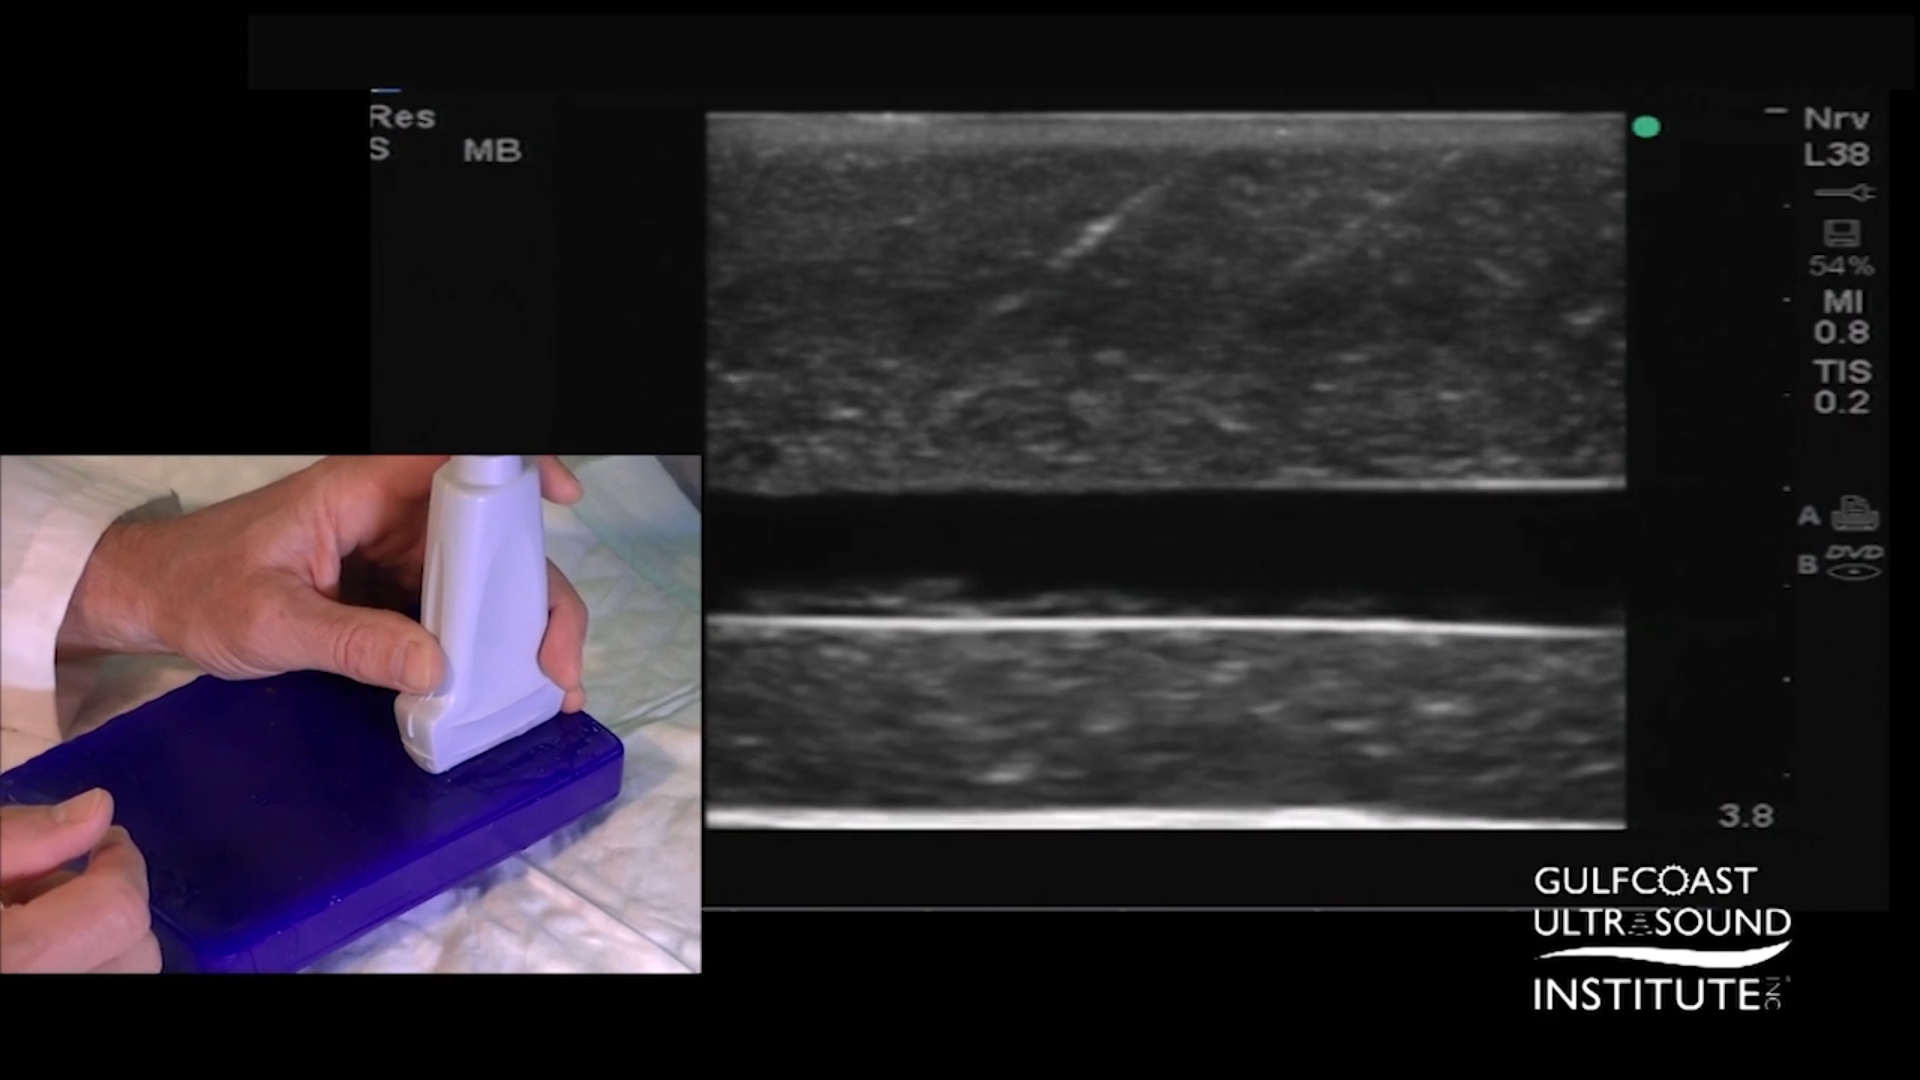

Start advancing the needle from the edge of the probe at a 45-degree angle. At this angle, you’ll see the needle enter from the side of the imaging field, providing a clear visual of the tip. With each advancement, employ a gentle side-to-side fanning motion, which will help you identify the needle tip as it moves through the imaging plane. The goal is to keep the needle tip bright in the image. If the tip remains clearly visible, continue advancing toward the target structure.